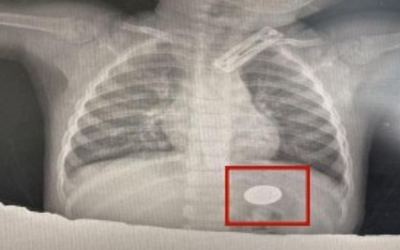

Nam sinh 16 tuổi, cao 1m60, nặng 120kg, có thể ăn hết 8 chiếc đùi gà nướng trong một buổi tối. Hễ có tiền tiêu vặt là mua gà rán, gà chiên giòn, cơn thèm ăn gần như không thể kiểm soát.